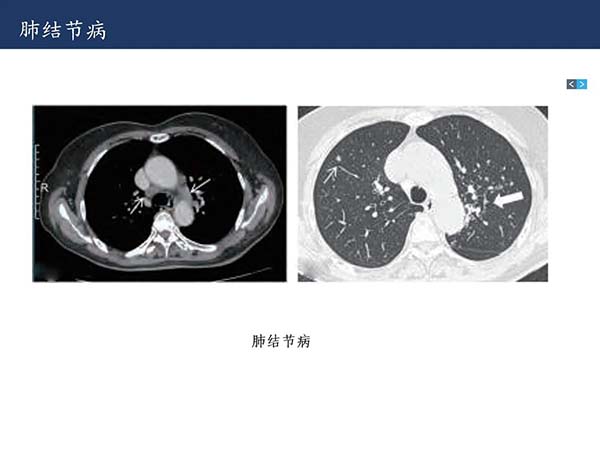

【杨柳科普】肺上皮样血管内皮瘤的影像表现